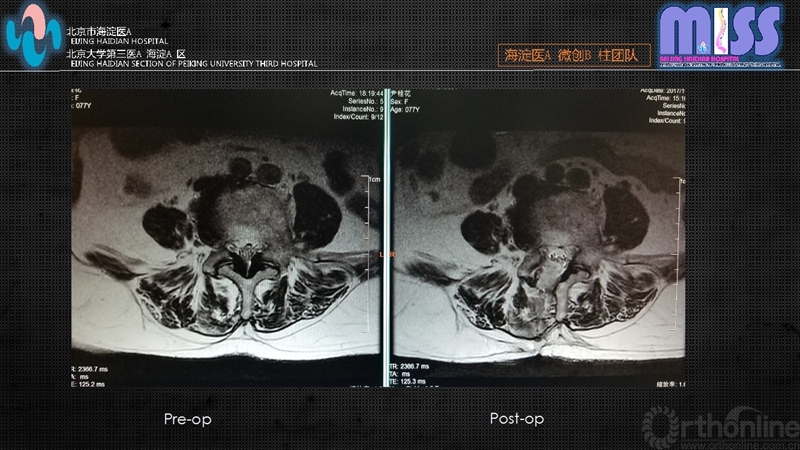

骨性结构清理结束后咬除入路侧全部黄韧带暴露硬膜囊,将工作套管向对侧倾斜约20~30°,磨钻适度去除棘突基底部骨质,暴露对侧硬膜及侧隐窝,应用Kerrison咬骨钳咬除对侧黄韧带,磨钻处理对侧增生内聚的上关节突内侧骨质,双侧减压范围:上界为黄韧带止点,下界为椎弓根上缘,外侧边界为神经根或硬膜外缘。术中见硬膜囊膨隆无压迹,神经根无卡压。必要时可采用术中透视确定减压范围。双极射频严密止血后停止灌注,观察有无活动性出血,如无活动性出血,拔出工作套管,缝合皮肤。

本组全部患者在12个月内得到完整随访,术后12个月时改良Macnab疗效评定:优24例,良6例,可4例,优良率88%。

通过对本组病例的随访观察,全内窥镜下单侧入路双侧减压技术,对老年中央型椎管狭窄及侧隐窝狭窄患者具有独特的优势,如:对患者全身情况要求低,术后恢复快,减少老年患者卧床并发症且该技术无需剥离椎旁肌,对腰椎后柱结构及肌肉韧带复合体破坏小。